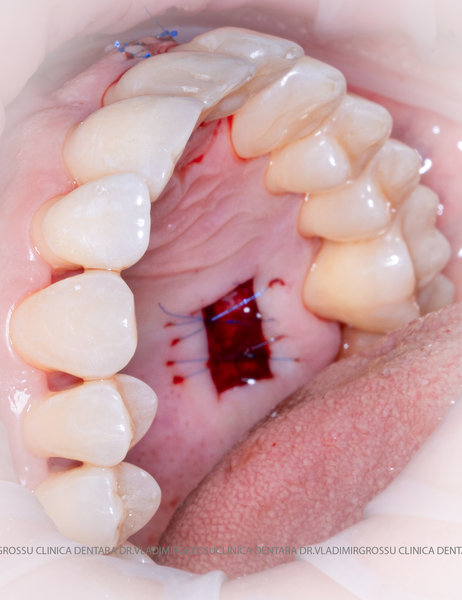

Un element esențial în procedura de aditie osoasă este utilizarea membranelor biologice, care izolează materialul osos de țesuturile moi (gingie) pe durata procesului de vindecare. Cele mai recomandate sunt membranele resorbabile din colagen sau pericard.

Aditia gingivală este o procedură chirurgicală ce corectează diverse probleme estetice și funcționale, cum ar fi recesiunea gingivală. În implantologia modernă, aditia de țesut moale este utilizată aproape în fiecare intervenție de inserție a implantului dentar pentru a asigura un aspect estetic natural și o bună integrare a implantului în cavitatea bucală.

Adiția osoasă are un rol crucial pentru poziționarea corectă și stabilă a implanturilor dentare. Clinica stomatologică Dr. Grossu din Chișinău promovează o abordare chirurgicală estetică și predictibilă, adaptată fiecărui caz în parte.